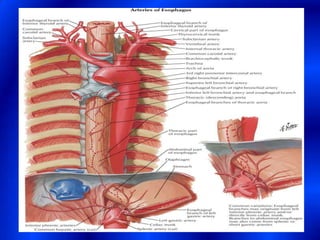

This document provides information about a barium swallow procedure. It begins with an introduction and overview of the embryology and anatomy of the pharynx and esophagus. It then describes the procedure itself, including preparation, technique, views obtained, and indications. Specific conditions that may be examined include pharyngeal and esophageal webs, foreign body impaction, scleroderma, dysphagia, mediastinal masses, and carcinoma. Diagrams are provided to illustrate normal anatomy and various pathological findings.